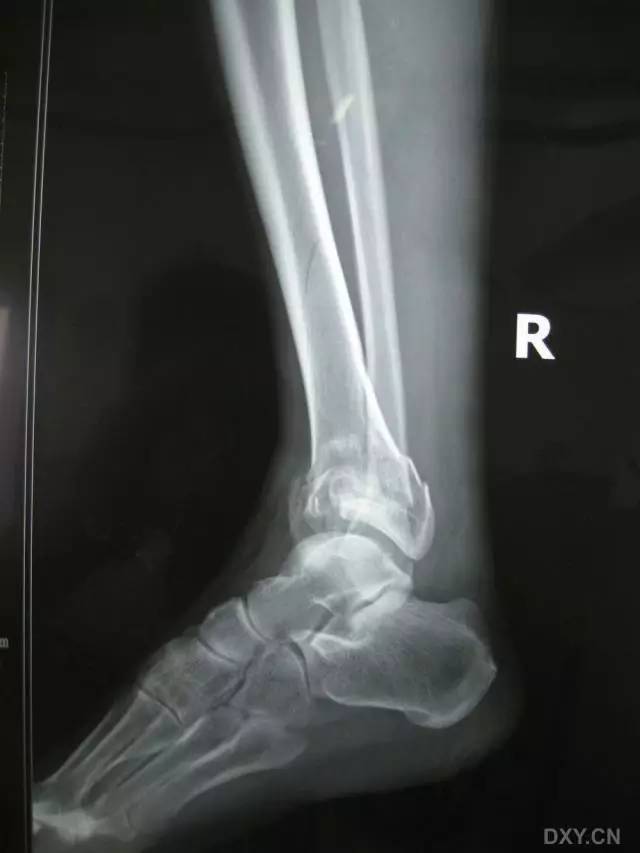

6. Pilon 骨折

涉及负重关节面(胫距关节面)与胫骨远侧干骺端的骨折。其典型特征是干骺端存在不同程度的压缩、干骺端的压缩粉碎性骨折不稳定、原发性关节软骨损伤以及永久性关节面不平整导致预后不良。

pilon 骨折正位片

pilon 骨折侧位片

pilon 骨折三维 CT 表现